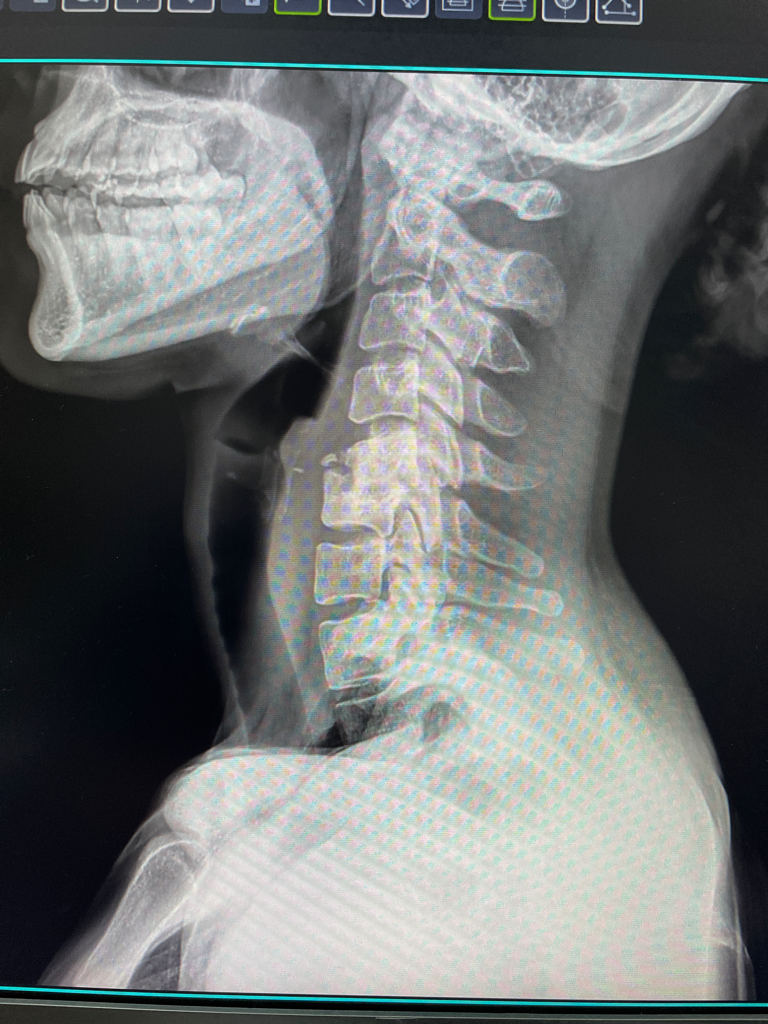

엑스레이상 경추 4,5번 골절인가요???

지난주부터 자는데 팔이 너무 아파서 자꾸 깨길래 오늘 병원에서 엑스레이를 찍었습니다. 사진상으로 골절로 보인다고 하시면서 큰병원 가보라고 하시면서 의뢰ㅛㅓ 작성해주셨는데..... 너무 놀라서 저도 모르게 울었는데 ㅋㅋㅋ 혹시 골절이라면 제가 큰 병원에서 정확히 확인 전까지 주의해야할 점이 있나요? 알고나니 조심스러워져서요 ㅎㅎ 선생님들의 고견이 궁금합니다..

경추 5번의 이상소견이 의심됩니다. CT검사를 통해 골절 여부 확인이 필요해 보이며 저림증이나 감각 이상이 있다면 서둘러 진료를 받기 바랍니다.

4, 5번이 아니고 경추 5, 6번 경추뼈의 몸통 두개가 형태가 변형되어 있습니다.

사고후에 찍은 엑스레이가 아니라면 혹시나 태어날때부터 기형으로 태어났을 가능성도 고려해볼 수 있겠습니다.

팔이 아픈 증상은 위 척추뼈 변형과 관련이 있을수도 있고 없을수도 있겠으며 경추 MRI 촬영을 통해서 신경이 어떻게 영향을 받고있는지를 확인하시는게 적절해보입니다.